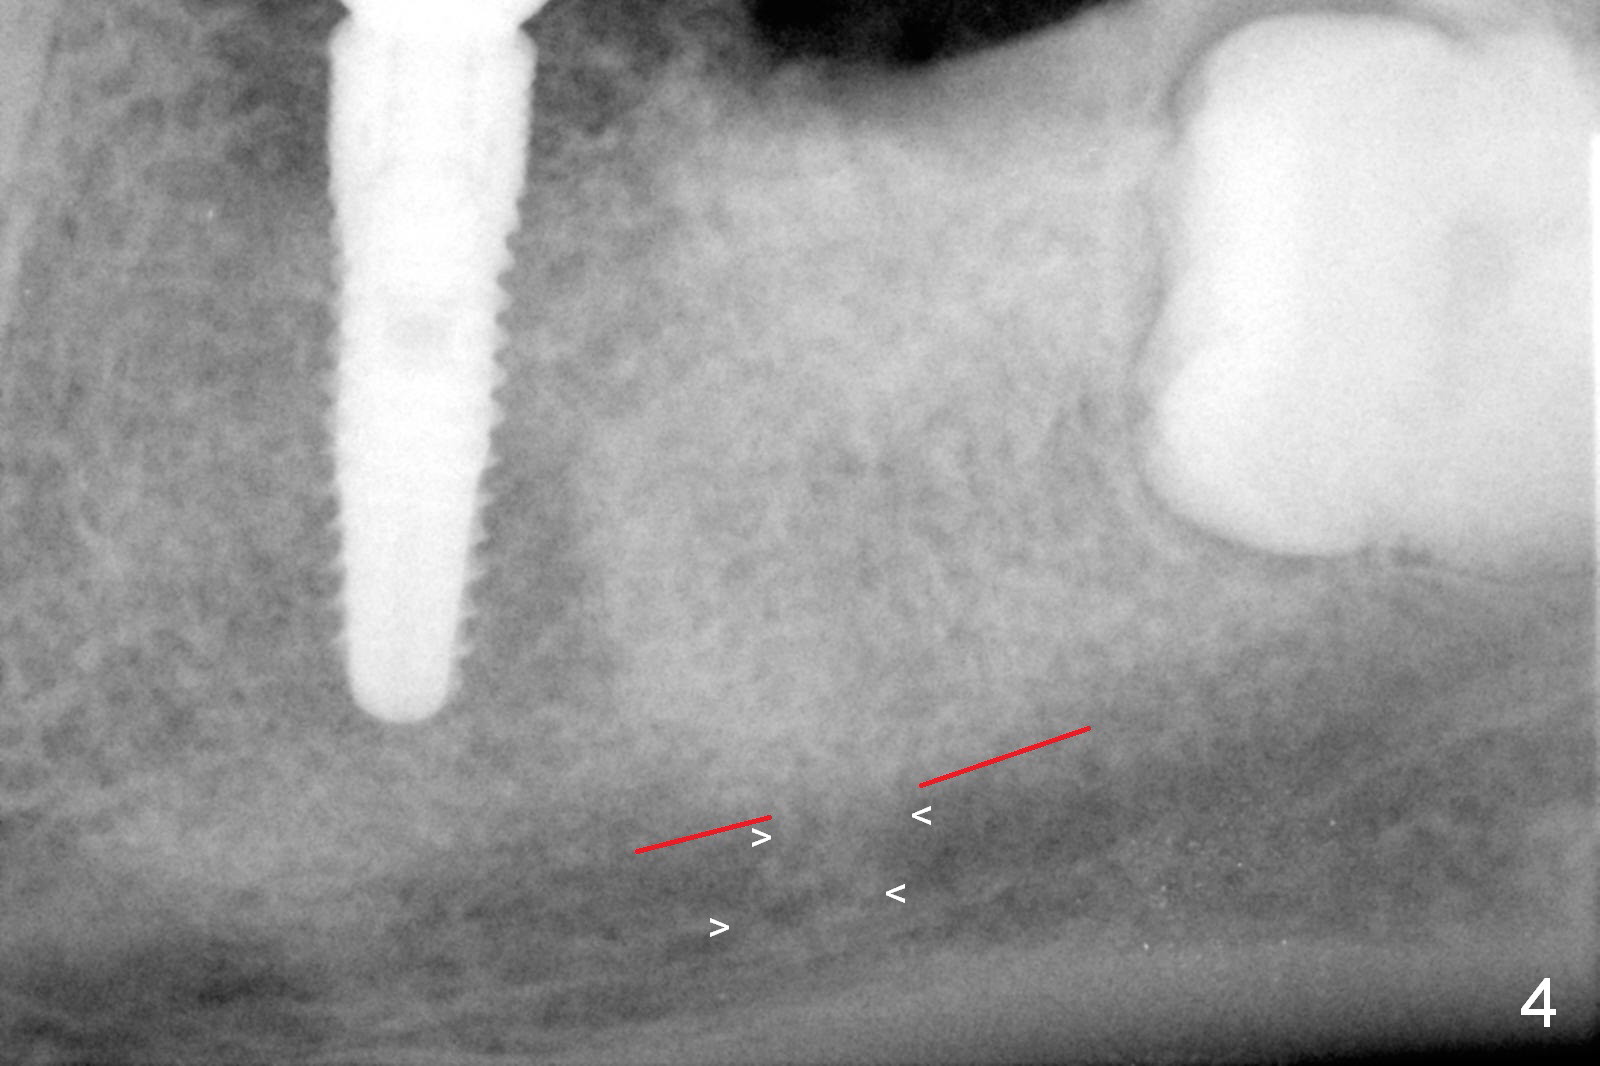

Infiltration anesthesia is enough for initial osteotomy at the site of #19 (Fig.1), but not for sectioning the tooth #18. Block anesthesia has to be administered. Fortunately it is safe to start osteotomy at #18 (~ 3 mm beyond the socket bottom, Fig.1 (red dashed line: the superior border of the Inferior Alveolar Canal (IAC))). A 4.5x14 mm implant is stable at #19, while a 5x12 mm one at #18 is not (Fig.2). Unfortunately bone graft has been placed. When the implant is removed, a 4.5x14 mm drill is used to deepen the osteotomy for 2 mm. The patient reports mild discomfort later on. Hemorrhage occurs, which is stopped when the same implant is re-placed. There is no stability. The implant is removed (Fig.3,4). More bone graft is placed, followed by collagen plug. It appears that bone graft has been pushed into the IAC (Fig.4 arrowheads). Medro dose pak is prescribed. In fact, no paresthesia is reported postop.